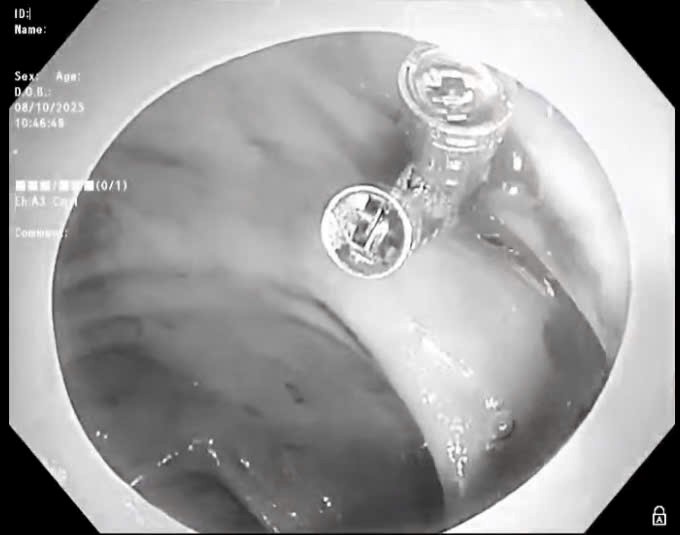

Sáng ngày 8/10, người bệnh được chỉ định nội soi đại tràng cấp cứu. Qua nội soi, quan sát thấy đại tràng có nhiều cục máu đông, tại vị trí túi thừa đại tràng ngang có điểm mạch, máu tươi chảy thành tia. Bác sỹ nội soi đã thực hiện cầm máu bằng 03 kẹp hemoclip. Sau can thiệp, tình trạng bệnh nhân hiện tại ổn định, đang được tiếp tục điều trị tại bệnh viện.

Theo BSCKI Trịnh Thị Liễu - Trưởng khoa Khám bệnh, là bác sĩ trực tiếp nội soi cho biết: "Chảy máu túi thừa đại tràng là một biến chứng thường gặp trong chảy máu đường tiêu hóa, tỷ lệ khoảng 30-65%. Với trường hợp người bệnh P đang xảy ra tình trạng chảy máu cấp, máu phun thành tia, nếu không được cầm máu, xử lý kịp thời sẽ dẫn đến sốc mất máu, ảnh hưởng nguy kịch đến tính mạng."